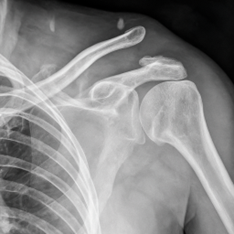

Пластика разрыва ключично-акромиального сочленения

Пластика разрыва ключично-акромиального сочленения — это хирургическая операция, направленная на восстановление стабильности плеча после травматического разрыва связок между ключицей и отростком лопатки (акромионом).